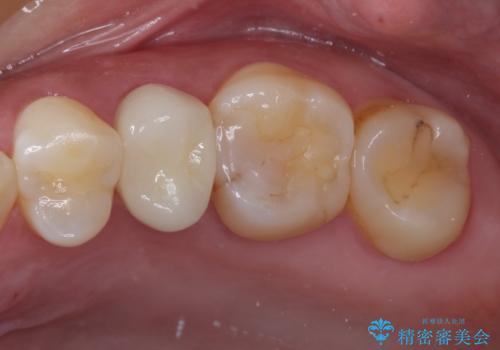

目立つ銀歯と欠けてしまった詰め物 オールセラミッククラウンでの補綴治療

不快感の強い奥歯 オールセラミッククラウンでのむし歯治療